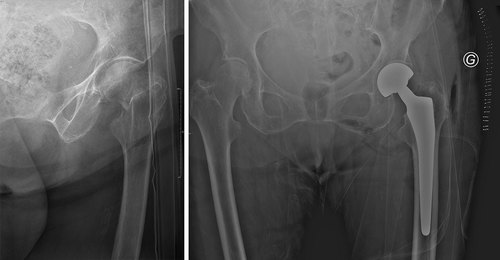

Fracture du col fémoral

Les indications sont portées sur le type de fracture observée à la radiographie, sur le capital osseux, et le terrain du patient.

L’ostéosynthèse : avec réduction de la fracture et mise en place de vis canulées de bon diamètre dans le col fémoral

L’arthroplastie : avec mise en place d’une prothèse de hanche, qu’elle soit totale ou intermédiaire avec une cupule cotyloïdienne mobile.

Le débricollage du matériel : lors de l’ostéosynthèse, on observe à la radiographie la mauvaise tenue des vis cervicales, avec nécessité de reprendre le patient pour mise en place d’une prothèse totale de hanche

Pseudarthrose : correspond à une mauvaise consolidation du trait de fracture malgré l’ostéosynthèse. Nécessite une reprise chirurgicale avec mise en place de prothèse totale de hanche.